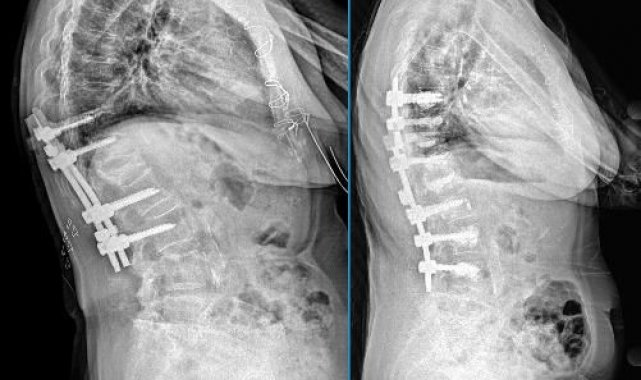

Hastanın durumu ile ilgili bilgi veren Kastamonu Eğitim ve Araştırma Hastanesi Ortopedi Uzmanı Op. Dr. Selahaddin Aydemir, "Yaptığımız tetkik ve incelemeler neticesinde tespit edilen ankilozon spondilit ve yaşadığı bir travma sonrası başka bir merkezde geçirdiği omurga ameliyatında kullanılan metal implantlar, tedavi gören 63 yaşındaki hastamızda zamanla implantların başarısız olması nedeniyle, hastamızın omurgasında belirgin bir kamburluk gelişmiş. Hastamızın ileri yaşta olması, mevcut ramotolojik hastalığı, kemik yapısında oluşan zayıflık, kamburluk sürecini de hızlandırdığını yaptığımız tetkiklerde gördük. Tabii hastamızın yaşam kalitesini olumsuz etkileyen bu durumunu hemen düzeltmek ve sağlığına kavuşturmak için kapsamlı bir cerrahi müdahale planladık. Omurgadaki eğriliği düzelterek, daha sağlam bir yapı oluşturmak için kemik çimentosuyla güçlendirilen vidalar kullanılarak omurgayı yeniden yerine sabitlendik. Başarılı geçen ve 3,5 saat süren yaptığımız bu operasyon sayesinde hastamızın omurga dengesi duruşu düzelerek günlük yaşam aktivitelerinde belirgin bir iyileşme kaydedildiğini söyleyebiliriz" dedi.